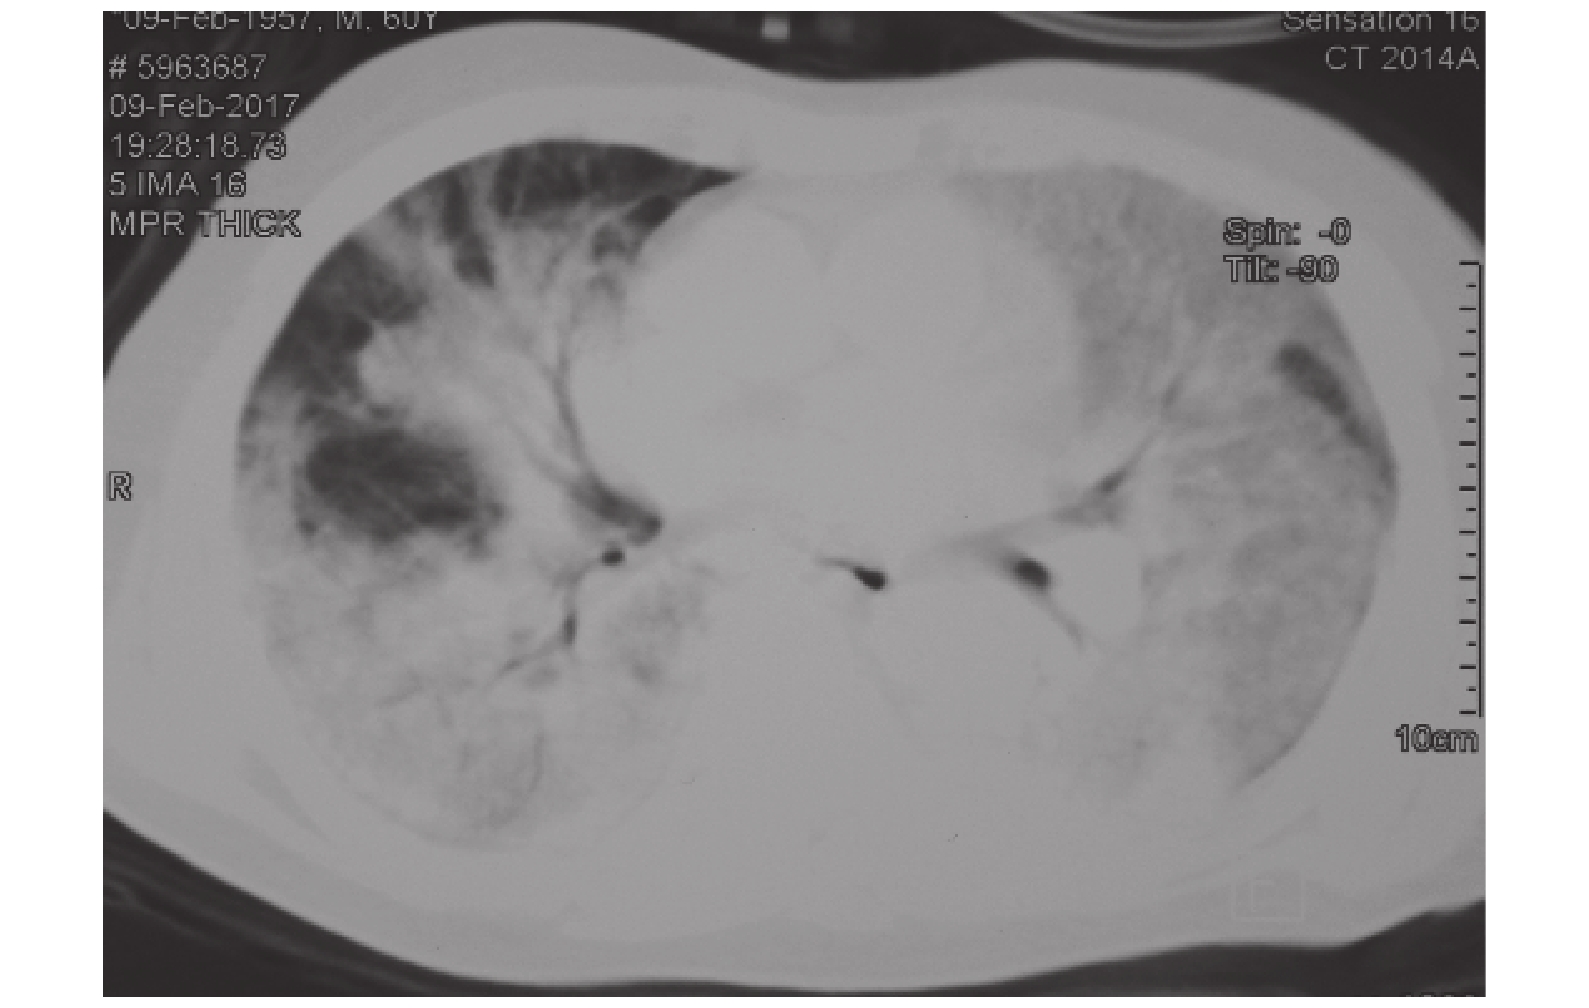

6 例肺部 CT 檢查具有共同特點:(1)病灶以下肺多見,可累計多個肺葉,多為一側肺表現明顯(圖 1~3);(2)主要影像表現有肺實變影、磨玻璃樣影(圖 4);(3)可合并胸腔積液(圖 5);(4)影像學征象變化迅猛,提示病情進展極快(圖 6)。

人感染 H7N9 禽流感患者在較短時間即可出現影像學改變,如肺實變、磨玻璃影等,多以下肺為主,侵犯雙肺多個肺葉,常以一側肺為重,常合并胸腔積液[5]。本組患者早期 5 例有胸腔積液,其中 3 例出現大量血性胸腔積液,提示病情極其危重。就目前救治工作進程初步總結,血性胸腔積液患者轉歸緩慢,提示血性胸腔積液可能伴隨較差的預后,因此需要積極干預。